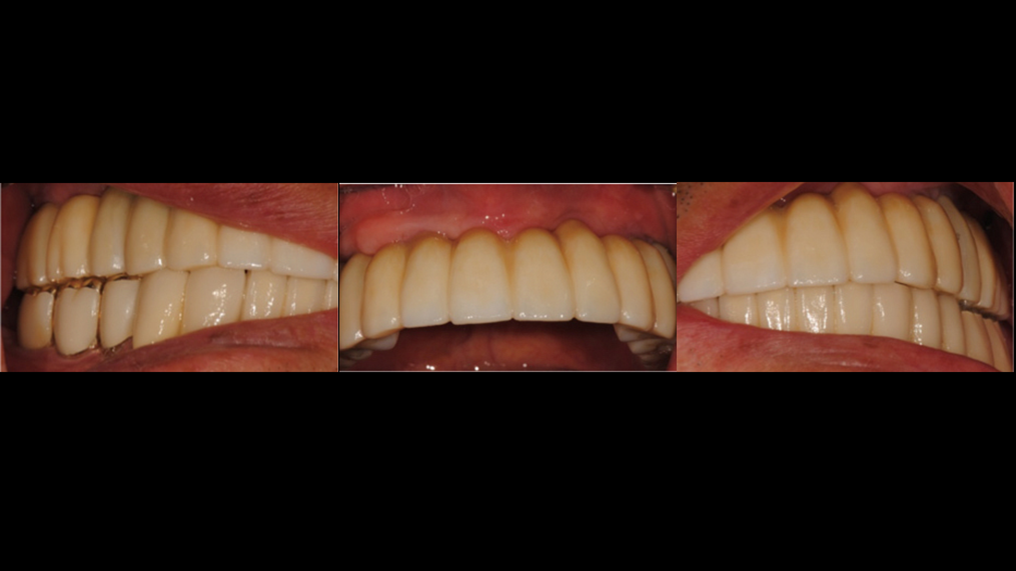

Clinical case: A Full transition from natural teeth to all-on-6 bridges

with AnyRidge implants

- Courtesy of Dr. Rabih Abi Nader, UAE -

Keywords

Full-mouth rehabilitation, minimal layering, Zirconia, all-on-6, life changing result, edentulous ,Dr. Rabih Abi Nader, AnyRidge

Products:

AnyRidge implant system

“AnyRidge shows excellent initial stability

& stable results after immediate loading in

upper fully edentulous case. ”